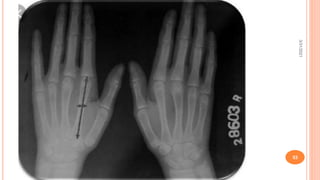

WORKUP

- Hand radiographs – arachnodactly shown by metacarpal index